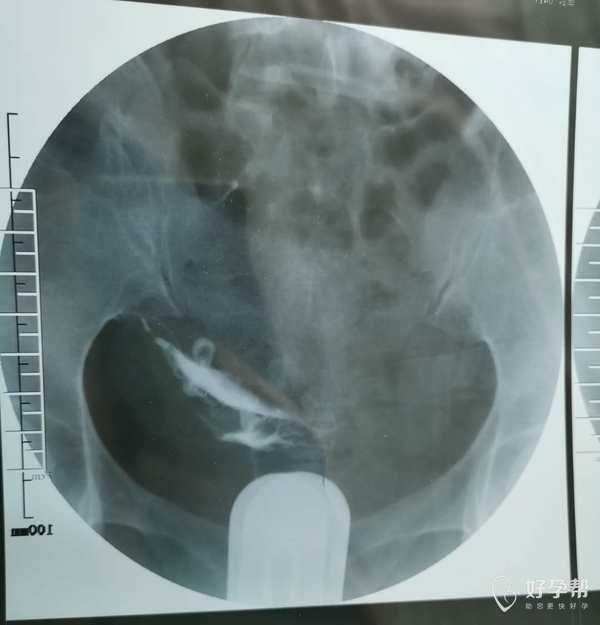

我这个是做了输卵管介入手术,请问输卵管是通了

你的片子提示双侧输卵管不通,未孕4年,合并腺肌症和腺肌瘤,建议你直接试管婴儿助孕。试管前不需要宫腹腔镜检查。